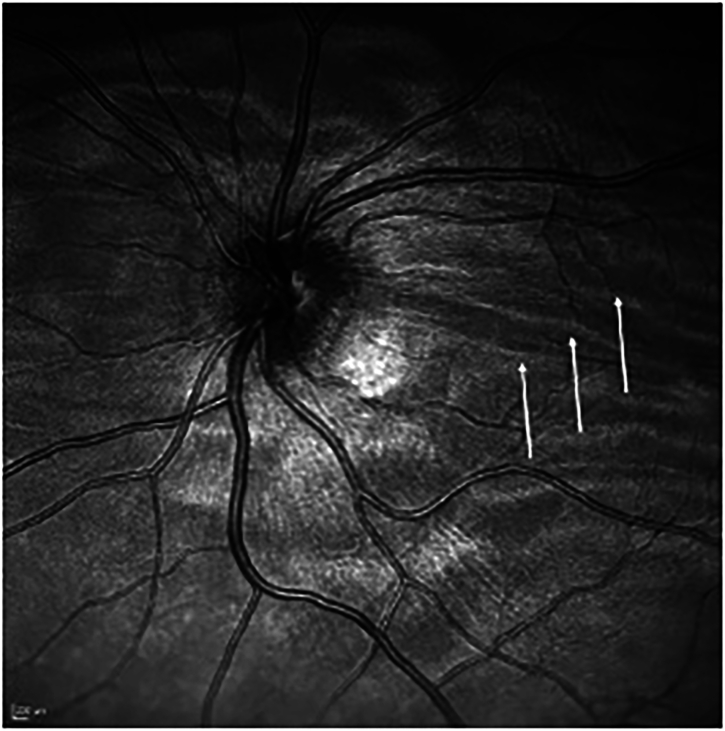

航天飞行相关的神经-眼综合征(SANS)影响宇航员的视力,在长时间任务期间和之后引起屈光和视力变化。随着太空机构计划扩展探索,实时SANS探测至关重要。对PubMed和EMBASE的系统回顾筛选了196项相关研究中的72项。目前的测量技术,包括有创和无创颅内压(ICP)评估和新技术,在量化SANS变化方面存在局限性,并且缺乏远程监测能力。诸如遥测ICP监测、光学相干层析成像(OCT)和超声等新兴工具显示出前景,但需要进一步验证。鉴于侵入性技术在空间中的局限性,非侵入性技术应在空间飞行实施之前在地面模拟物中进行测试。确切的SANS病因将决定最佳的监测方法,是icp为重点,眼为基础,还是两者结合。没有一种技术可以独立跟踪SANS进展,强调需要多参数集成和事后分析,以加强飞行中监测和缓解策略。

Spaceflight-Associated Neuro-Ocular Syndrome (SANS) affects astronaut vision, causing refraction and acuity changes during and after long-duration missions. As space agencies plan for extended exploration, real-time SANS detection is crucial. A systematic review of PubMed and EMBASE yielded 72 relevant studies out of 196 screened. Current measurement techniques, including invasive and noninvasive intracranial pressure (ICP) assessments and novel technologies, have limitations in quantifying SANS changes and lack remote monitoring capability. Emerging tools such as telemetric ICP monitoring, optical coherence tomography (OCT), and ultrasound show promise but require further validation. Given the constraints of invasive techniques in space, non-invasive technologies should be tested in terrestrial analogs before spaceflight implementation. The precise SANS etiology will determine optimal monitoring approaches, whether ICP-focused, ocular-based, or a combination of both. No single technology can independently track SANS progression, emphasizing the need for multiparametric integration and post hoc analysis to enhance in-flight monitoring and mitigation strategies.